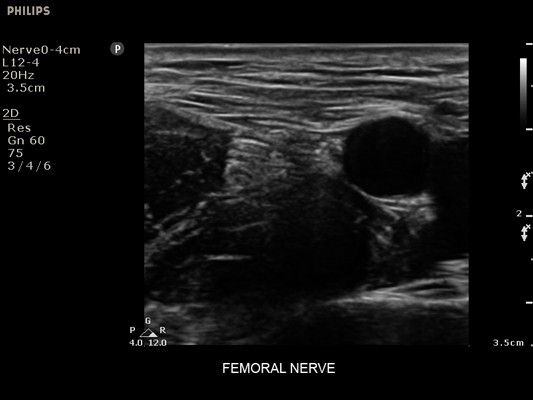

• Диагностика нервов

• Линейный УЗИ датчик Philips L12-4